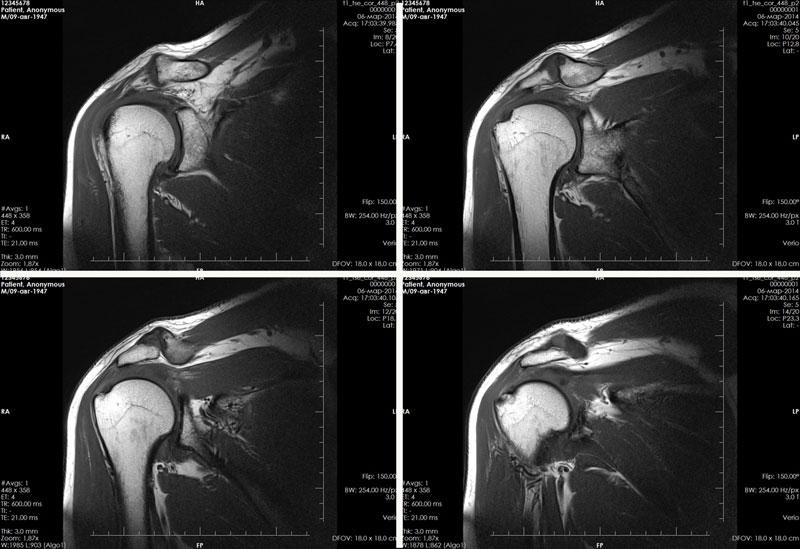

Анатомия плечевого сустава действительно сложна и включает множество структурных элементов (см. рисунок ниже). МРТ позволяет детально исследовать все компоненты и выявить возможные патологии и отклонения.

Что показывает и что можно обнаружить на МРТ плечевого сустава

Полученные изображения в различных срезах анализируются сразу или объединяются специалистом в одно трехмерное изображение исследуемой области (фото МРТ плеча можно найти в данном материале).

Что показывает МРТ плеча? Собранные данные позволяют врачу оценить и выявить следующие отклонения: